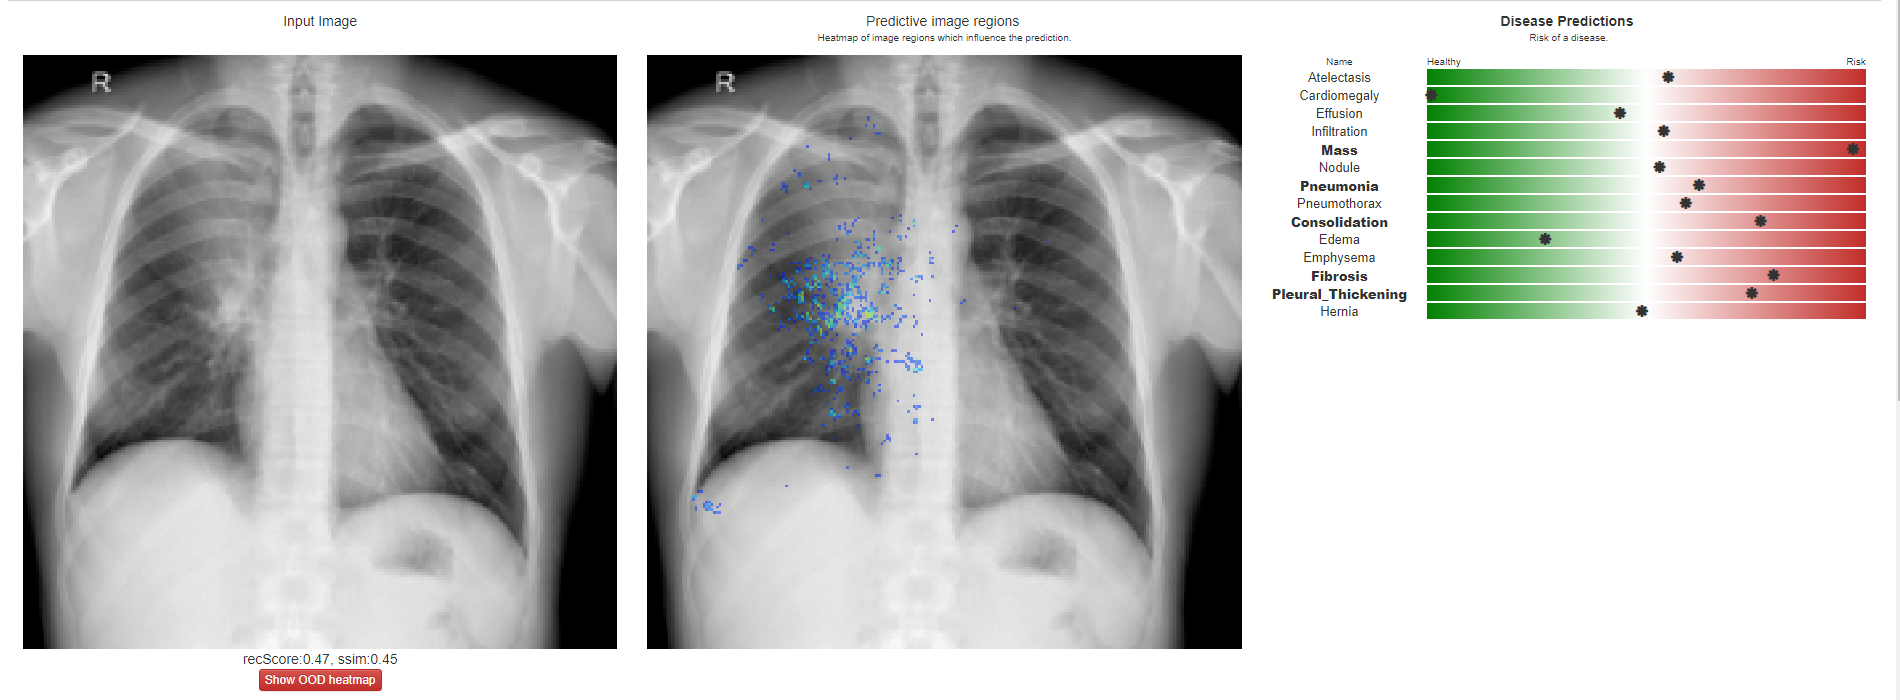

From medium.com

Evaluating chest xrays using AI in your browser? — testing Chester How To Evaluate A Chest X Ray The condition of your lungs. Doctors typically use this procedure to help diagnose breathing difficulties, a bad or persistent cough,. This chapter will review the key components of a systematic analysis of frontal chest radiographs by demonstrating normal and abnormal radiographic findings. There is no one recommended analysis methodology; Abcdefghi can be used to guide a systematic. Trachea, carina, bronchi. How To Evaluate A Chest X Ray.